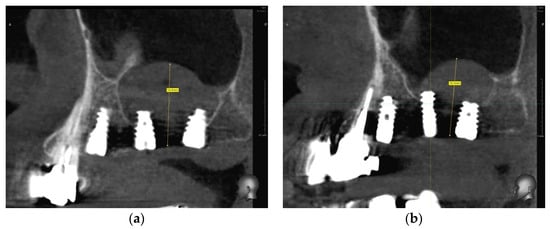

1. Introduction

2.6. Case Study